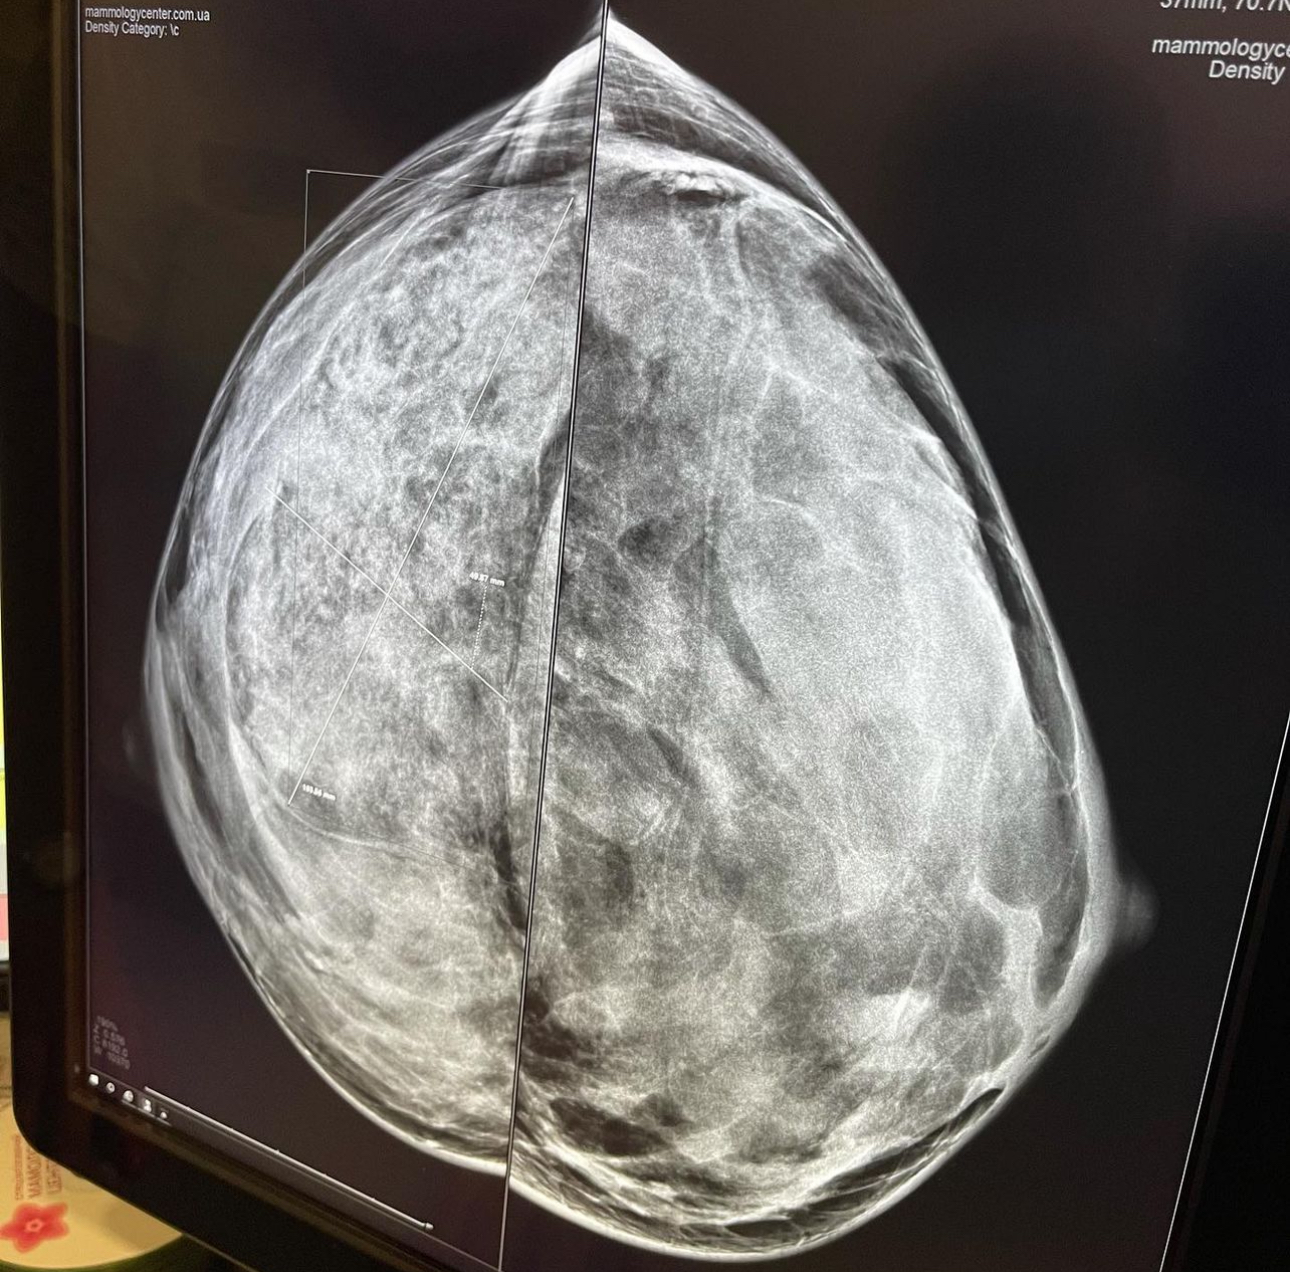

Процедура мамографії проводиться на стаціонарному апараті. Для цього жінці потрібно буде роздягнутися до пояса, зняти будь-які прикраси з шиї. Потім вас попросять затримати дихання на кілька секунд, поки апарат робить знімок грудей.

В результаті обстеження лікар одержить знімок, на основі якого і буде поставлено діагноз.